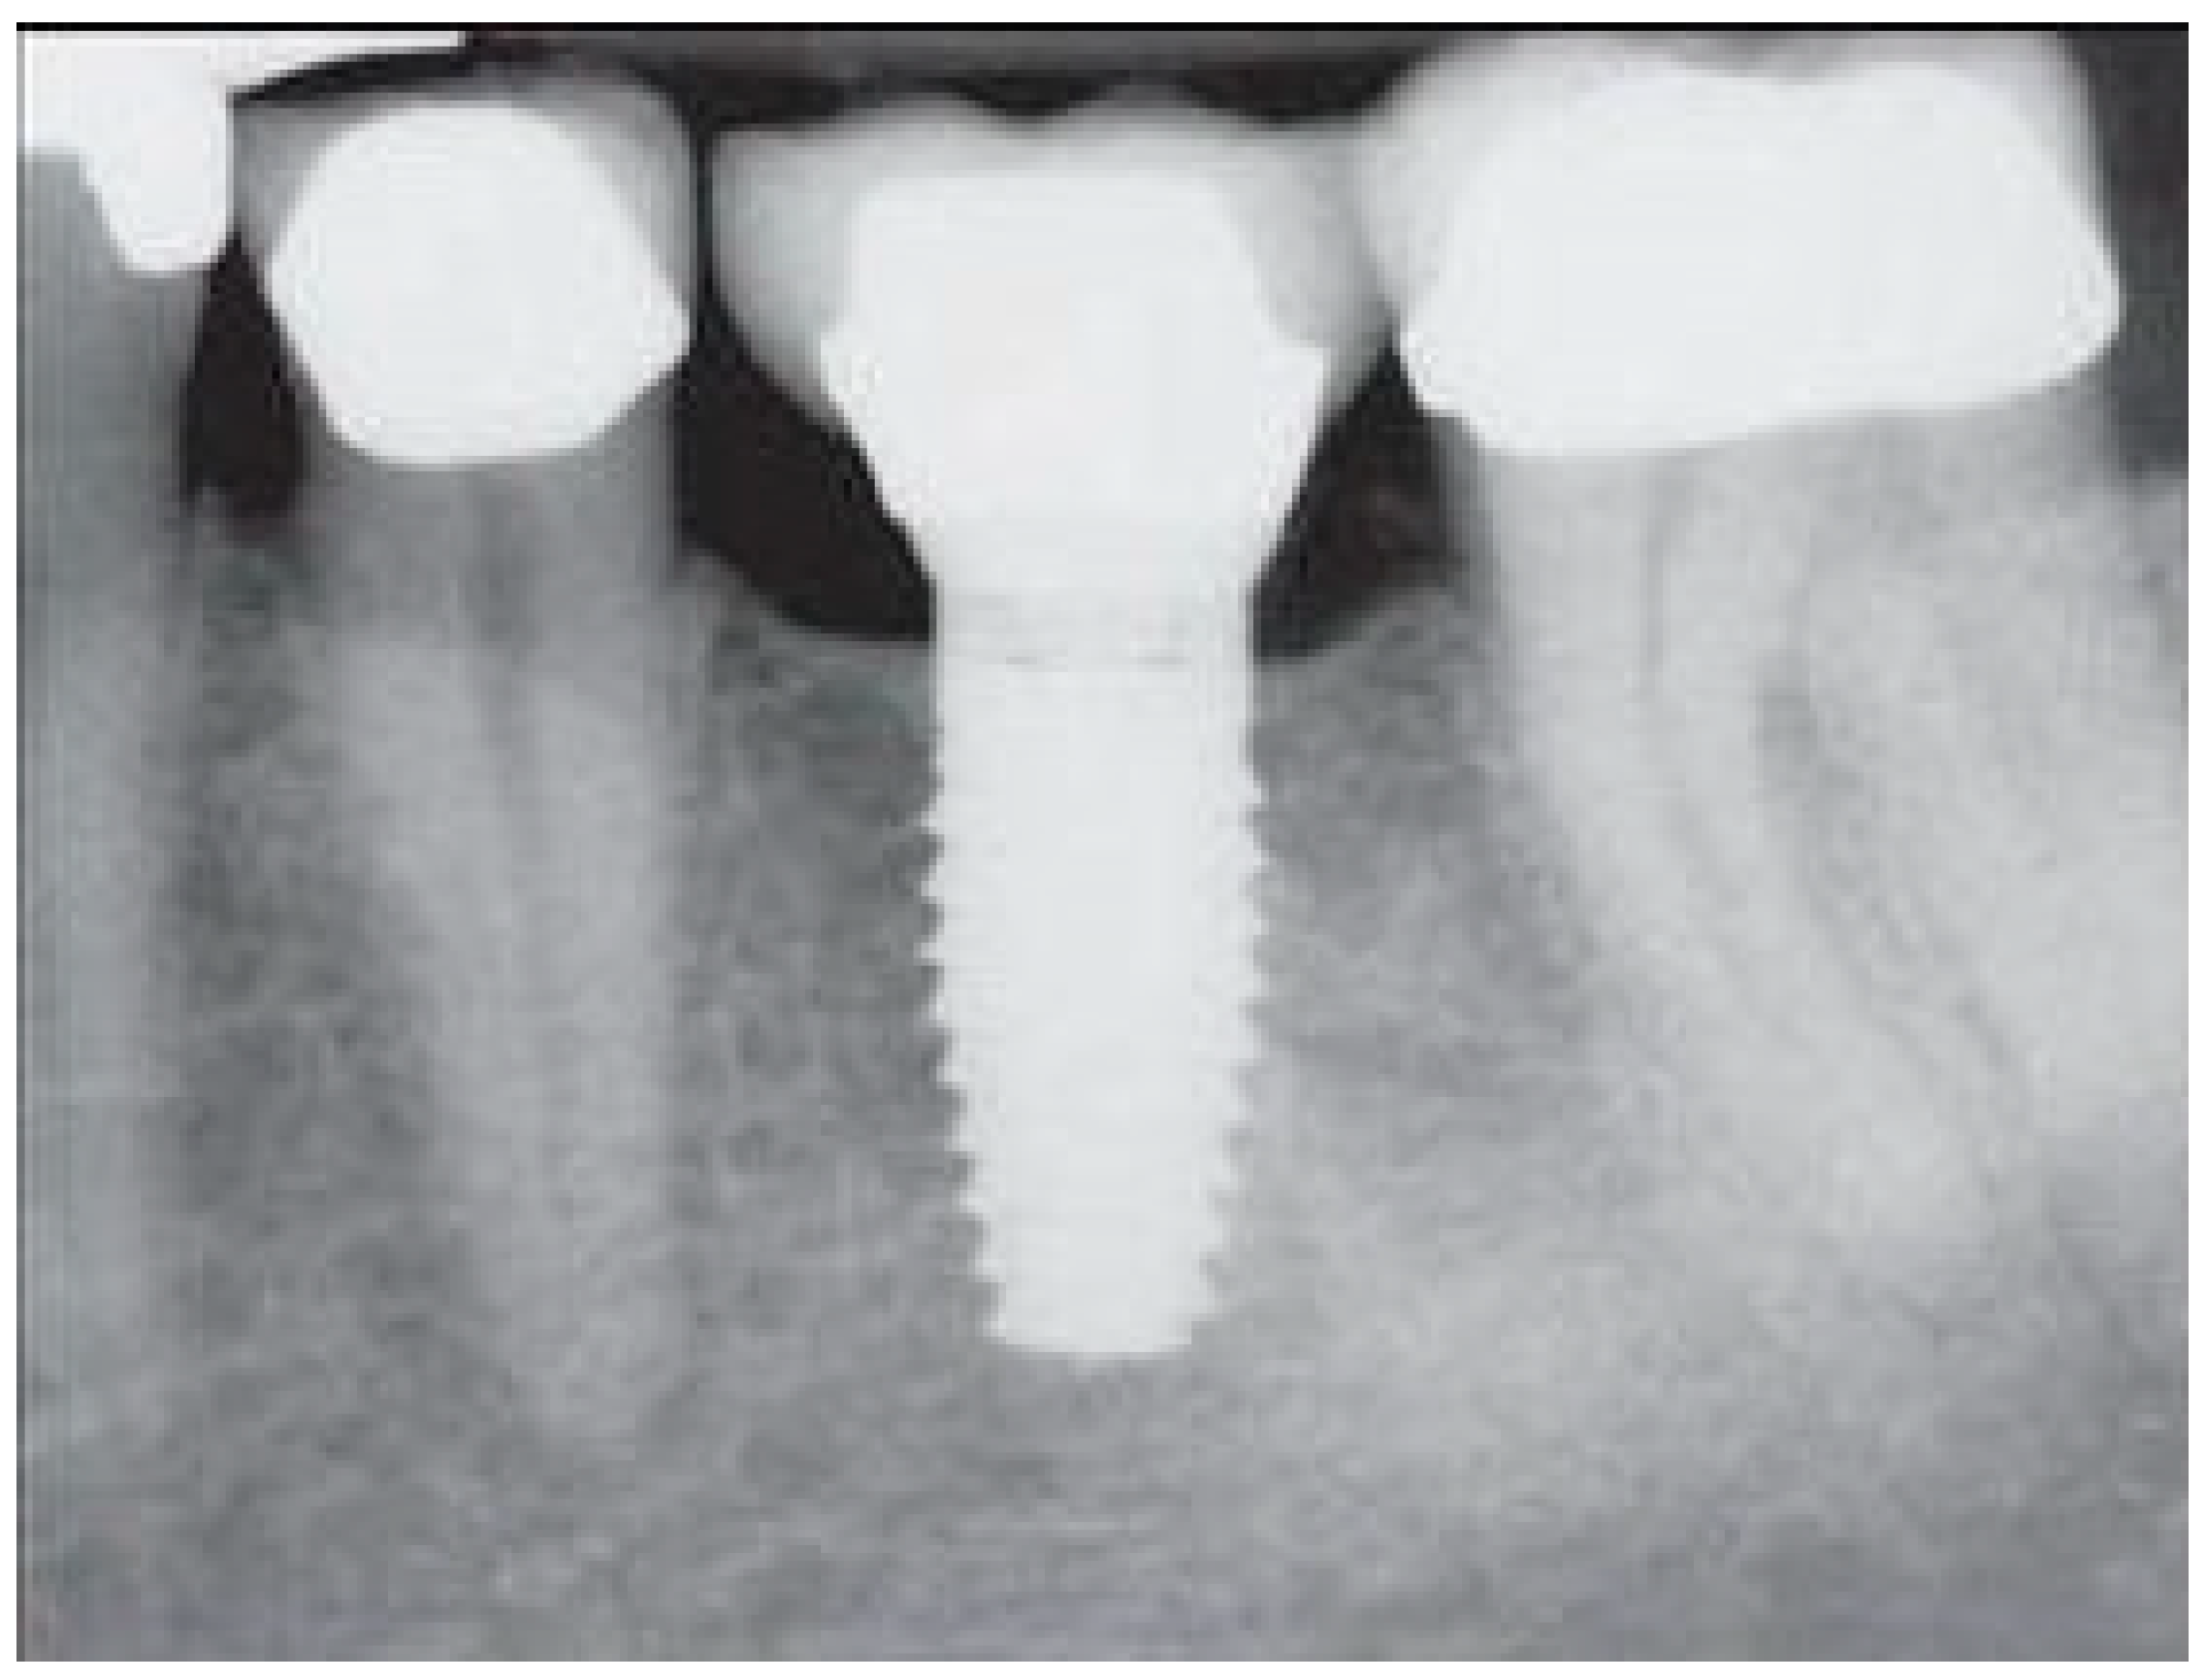

- Measurement of mesial and distal bone loss: Clinically, an increase in the probing depth of the peri-implant pockets, both mesial and distal, was recorded using a calibrated probe with a force of 0.25 N. Radiographically, mesial and distal peri-implant bone height loss was measured using properly performed radiological projections. In fewer than five patients, statistically significant findings in cases of bone loss were difficult to achieve.